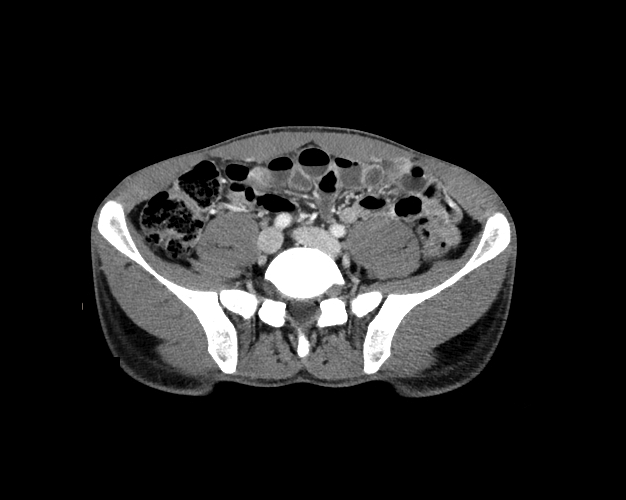

Body

Covers abdominal CT anatomy.